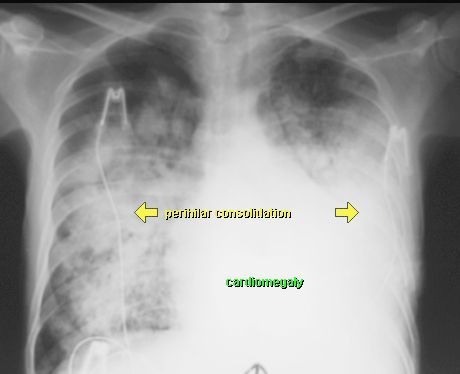

OBRZĘK PŁUC

RTG